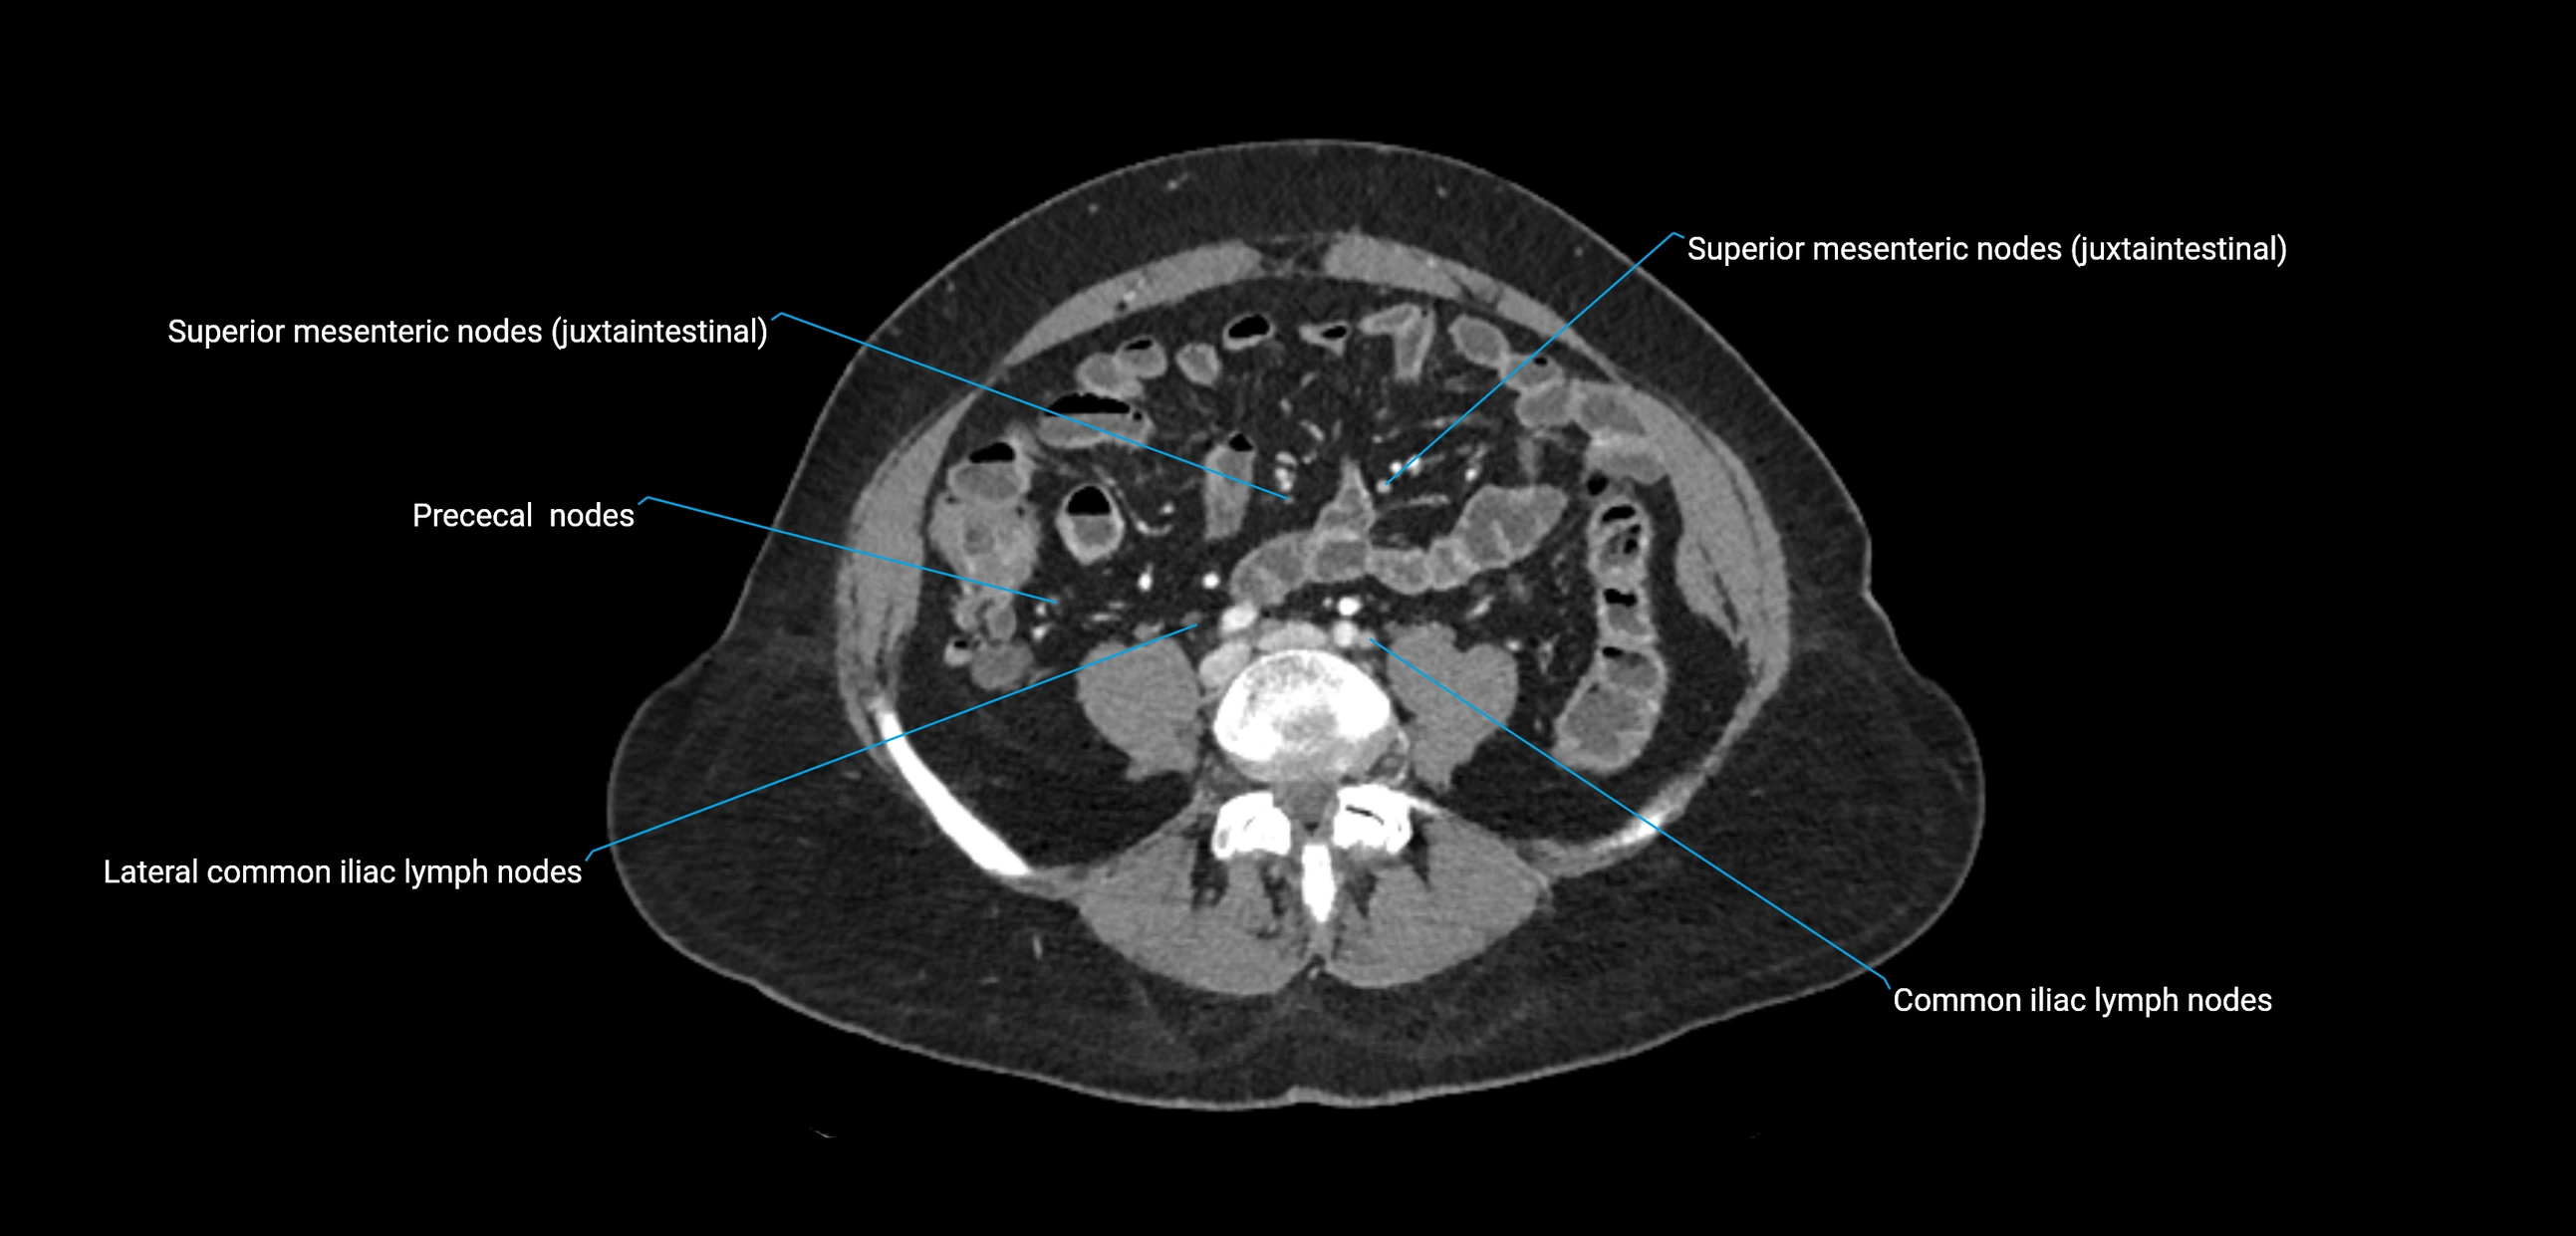

CT image

image